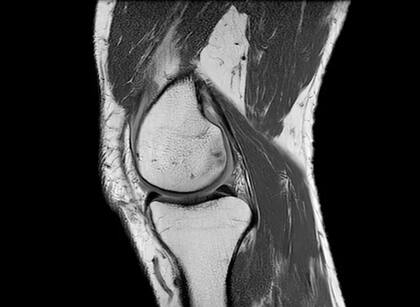

Nuestras rodillas dependen especialmente de cuatro grupos de músculos que las rodean: los isquiotibiales, los de los glúteos, los cuádriceps y los músculos de la pantorrilla. Esos grupos de músculos le permiten estabilidad y le dan la capacidad de absorción para poder funcionar.

“Cuando esos músculos no están interactuando y trabajando juntos, la articulación recibe más presión. Ahí es cuando comenzamos a sentir el dolor”, señala Chhabra.

Las investigaciones muestran que el estiramiento de ese grupo de músculos a través del ejercicio puede evitar la degeneración del cartílago en la rodilla, que es lo que luego puede conducir a una osteoartritis. Esto también puede servir para retrasar o incluso prevenir una cirugía de reemplazo en la rodilla.

Otros estudios señalan que mantener estos músculos fuertes puede reducir la carga de la rodilla y el dolor en pacientes que están en las primeras etapas de la osteoartritis.